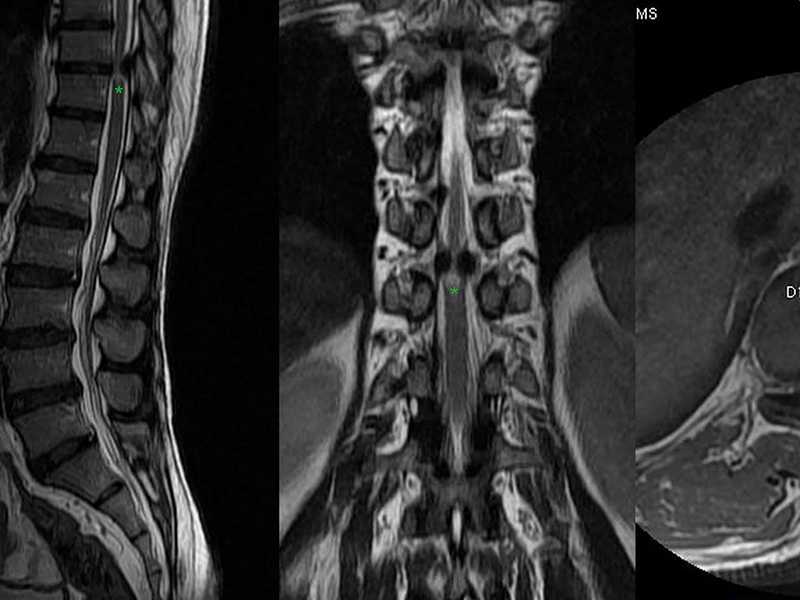

Lomber MR, bel fıtığı, omurga tümörleri, spinal stenoz, enfeksiyonlar ve dejeneratif disk hastalıkları gibi birçok hastalığın teşhisinde kullanılır. Bu hastalıkların yanı sıra sinir sıkışmaları ve omurga yaralanmaları da bu yöntemle tespit edilebilir.

Lomber MR’da omurga, diskler, sinirler ve çevre dokuların durumu detaylı bir şekilde görüntülenir. Bel fıtığı, disk kayması, tümörler, enfeksiyonlar ve sinir sıkışmaları gibi durumlar net bir şekilde görülebilir. Bu sayede doğru tanı konulabilir ve uygun tedavi planı oluşturulabilir.